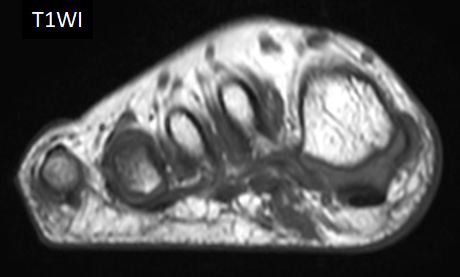

8歳男児 歩行時痛、足底部腫瘤

T1WI

- 【参考症例】